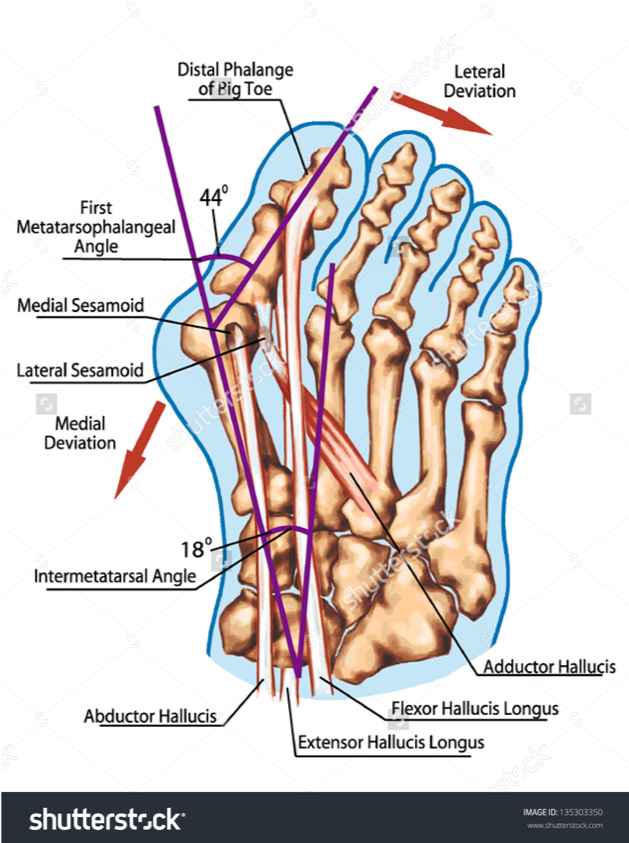

Hallux valgus is a progressive foot deformity in which the first metatarsophalangeal (MTP) joint is affected and is often accompanied by significant functional disability and foot pain. This joint is gradually subluxed (lateral deviation of the MTP joint) resulting in an resulting in an abduction of the first metatarsal while the phalanges adduct. This often leads to development of soft tissue and bony prominence on the medial side of what is called a bunion

what is the pathogenesis of hallux valgus?

Lateral angulation of great toe

Tendons pull realigned to lateral of centre of rotation of toe worsening deformity

Vicious cycle of increased pull creating increased deformity

Sesamoid bones sublux (medially) – less weight goes through great toe

As deformity progresses abnormalities of lesser toes occur